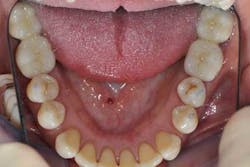

Figs. 9a, b, and c: Two years’ postop. Note the patient’s commitment to maintaining an optimal oral hygiene